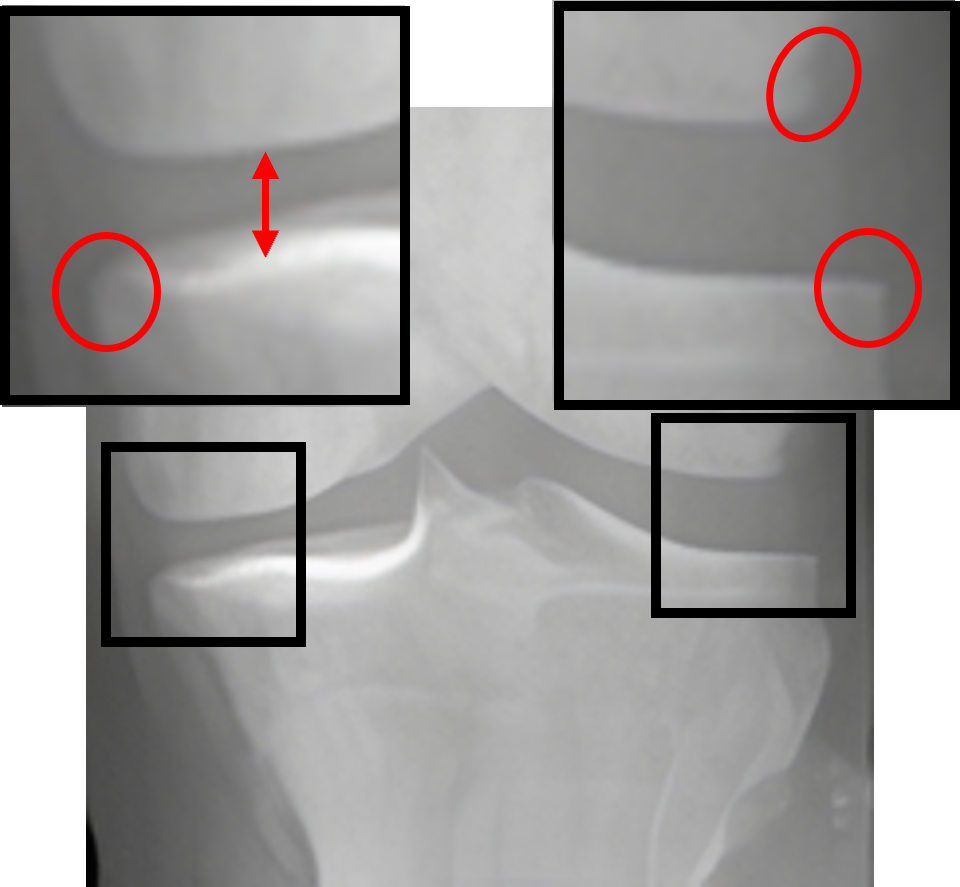

Table 2: Visualization of the synthesized intermediate frames

Input image Synthesized intermediate framessuperscriptSynthesized intermediate frames\stackrel{{\scriptstyle\text{Synthesized intermediate frames}}}{{\makebox[284.52756pt]{\rightarrowfill}}} Input image

xSsubscript𝑥𝑆x_{S} xS(φη=0.25)subscript𝑥𝑆subscript𝜑𝜂0.25x_{S}(\varphi_{\eta=0.25}) xS(φη=0.5)subscript𝑥𝑆subscript𝜑𝜂0.5x_{S}(\varphi_{\eta=0.5}) xS(φη=0.75)subscript𝑥𝑆subscript𝜑𝜂0.75x_{S}(\varphi_{\eta=0.75}) xTsubscript𝑥𝑇x_{T}

KL-0 KL-1∗∗ KL-2∗∗ KL-3∗∗ KL-4

[Uncaptioned image] [Uncaptioned image] [Uncaptioned image] [Uncaptioned image] [Uncaptioned image]

• *

The morphed areas of each frame were highlighted within black boxes, the red arrow and red circle indicate the locations of JSN and osteophyte formation, respectively. A shorter arrow indicates a smaller joint space (i.e., a narrower distance between the tibia and femur), while a larger circle indicates more osteophytes.

• **

The expected labels.

4.2 Visualization of the synthesized intermediate frames

In Table 2, we show the source image xSsubscript𝑥𝑆x_{S}, the target image xTsubscript𝑥𝑇x_{T}, and their intermediate frames (i.e., xS(φη=0.25)subscript𝑥𝑆subscript𝜑𝜂0.25x_{S}(\varphi_{\eta=0.25}), xS(φη=0.5)subscript𝑥𝑆subscript𝜑𝜂0.5x_{S}(\varphi_{\eta=0.5}) and xS(φη=0.75)subscript𝑥𝑆subscript𝜑𝜂0.75x_{S}(\varphi_{\eta=0.75})), which is crucial in understanding how the source images evolve into their registered state. The progressive alignment is quantified by the parameter η𝜂\eta evenly divided into 0.25, 0.5, and 0.75, which represents the extent of transformation at each stage of KOA, corresponding to KL-1, KL-2, and KL-3, respectively. As can be seen, xS(φη=0.25)subscript𝑥𝑆subscript𝜑𝜂0.25x_{S}(\varphi_{\eta=0.25}) shows the initial stage of the morphing process where the morphs are minimal and closely resemble the source image. For xS(φη=0.5)subscript𝑥𝑆subscript𝜑𝜂0.5x_{S}(\varphi_{\eta=0.5}), the morph is more pronounced, introducing clear signs of osteophytes and beginning to show a narrowing of the joint space. It is noteworthy that this frame is critical as it represents the halfway anchor point of the KOA temporal evolution process, showing a balanced mix of characteristics from both the source and target images. xS(φη=0.75)subscript𝑥𝑆subscript𝜑𝜂0.75x_{S}(\varphi_{\eta=0.75}) signifies an advanced stage of morph, introducing moderate multiple osteophytes, definite narrowing of the joint space, some sclerosis, and possible deformity of bone contour.